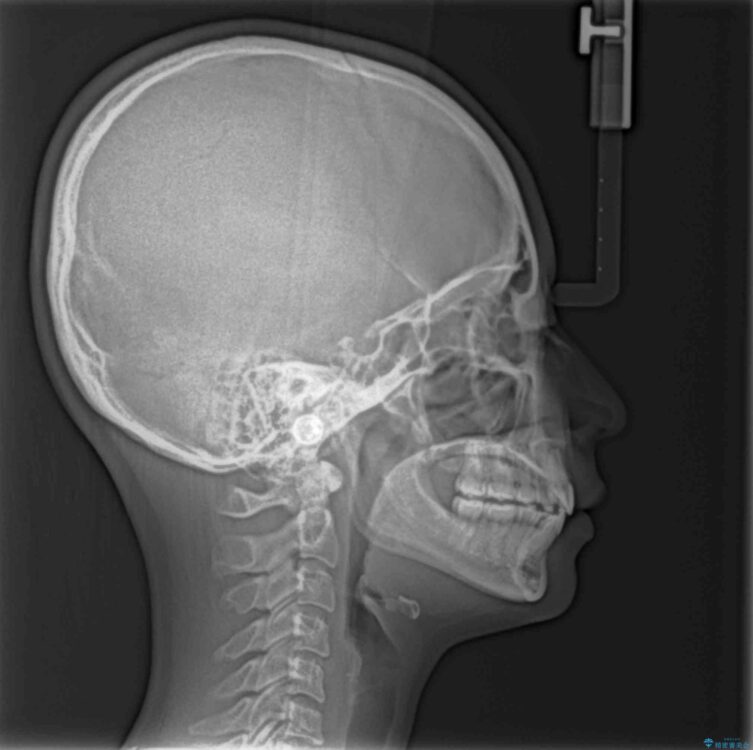

治療後

• 【モニター】口が閉じられない ワイヤー装置での抜歯矯正 治療後画像

舌の突出癖があり、前歯の移動量も多くなるため、治療期間は長くなると予想されましたが、13ヶ月という予定の半分程度の期間で終えることができました。

上下前歯が著しく前突している状態であったので、上下左右の第1小臼歯4本を抜歯し、ワイヤー装置にて矯正治療を行うこととしました。